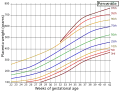

Placenta weight by gestational age[59]